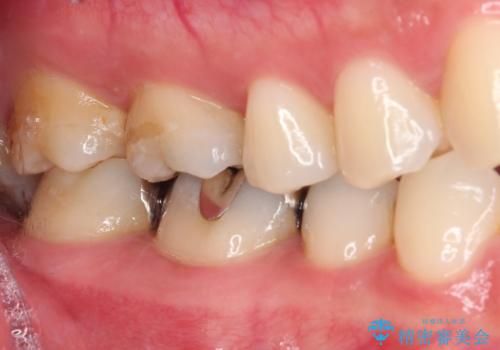

- 銀歯をセラミックにしたいとのことで来院された患者様です。

まず麻酔をして銀歯を外し、むし歯を除去し、形を整えて型取りします。

そして次の来院時、セラミックインレーを装着し、噛み合わせなどの調整を行います。

それを左右に分けて行いました。

インレーを装着するときは、唾液や血液による接着力の低下を避けるためにラバーダム防湿を行いました。